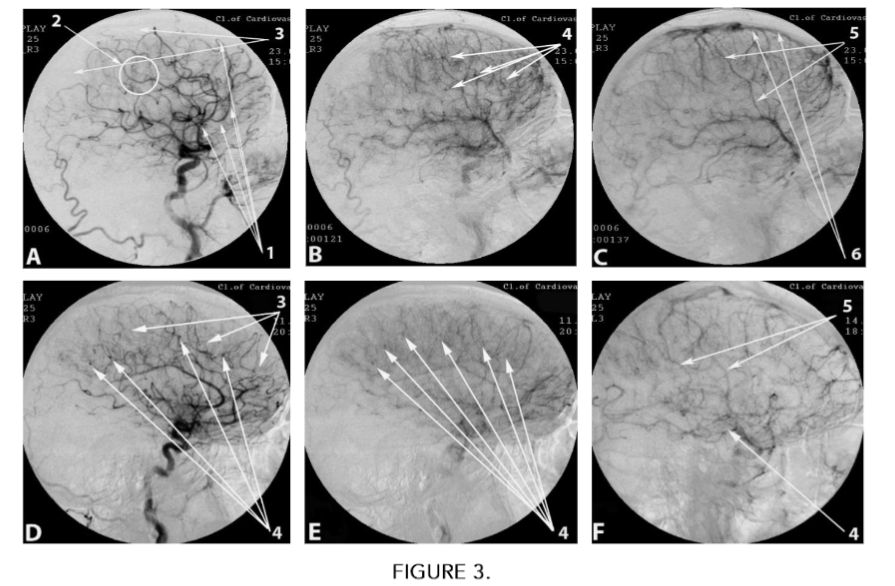

Atherosclerotic changes in the intracerebral distal arterial and capillary bed were detected in 931 (100%) cases (Table 2).

Atherosclerotic stenosis of intracerebral distal arterial branches and capillaries was detected in 931 (100%) cases (Fig. 3 A(1)) (Table 2).

Atherosclerotic occlusions of distal arterial branches and capillaries at the level of the gray cerebral matter were detected in 348 (37.38%) cases (Fig. 3 A(2)) (Table 2).

Decreased capillary blood flow at the level of the gray cerebral matter in 768 (82.49%) cases (Fig. 3 A(3)) (Table 2).

Multiple, disseminated arteriovenous shunts of small diameter within the gray matter of the brain were detected in 386 (41.46%) cases (Fig. 3 B(4)) (Table 2).

Subcortical, disseminated early flow of arterial blood into the venous bed, without the development of abnormal venous trunks and venous blood stasis, was detected in 245 (26.32%) cases (Fig. 3 C(5)), (Fig. 3 C(6)), (Table 2).

Subcortical disseminated and local decrease in capillary blood flow at the level of the cerebral white matter

- Subcortical disseminated decrease in capillary blood flow at the level of the white matter of the brain was detected in 89 (9.56%) cases (Fig. 3 D(3)), (Table 2).

- Subcortical, disseminated, multiple small-diameter arteriovenous shunts at the level of the white matter of the brain were detected in 27 (2.90%) cases (Fig. 3 D(4)), Fig. 3 E(4)), (Table 2).

- Subcortical, multiple, disseminated, early flow of arterial blood into the venous bed at the level of the white matter of the brain was detected in 27 (2.90%) cases (Table 2).

- Subcortical, single, local arteriovenous shunts of small diameter within the white matter of the brain in the area of the pons, thalamus, and basal ganglia were detected in 62 (6.66%) cases (Fig. 3 F(4)), (Table 2).

- Subcortical, local, early flow of arterial blood into the venous bed at the level of the white matter of the brain was detected in 62 (6.66%) cases (Fig. 3 F(5)), (Table 2).

FIGURE 3

Cerebral MUGA of patients with distal cerebral atherosclerosis.

A. Arterial phase:

- Atherosclerotic changes in intracerebral branches.

- Atherosclerotic occlusions of distal arterial branches and capillaries at the level of the cerebral gray matter.

- Decreased capillary blood flow at the level of the cerebral gray matter.

B. Parenchymal stage:

4. Multiple small-diameter arteriovenous shunts.

C. Venous phase:

5. Disseminated early flow of arterial blood into the venous bed without the development of abnormal venous trunks.

6. No venous blood stasis.

D. (BD). Arterial phase:

3. Decreased capillary blood flow at the level of the white cerebral matter.

4. Multiple subcortical arteriovenous shunts of small diameter.

E. (BD). Parenchymal phase:

4. Multiple disseminated subcortical arteriovenous shunts of small diameter.

F. (VP). Parenchymal phase:

4. Single, local arteriovenous shunts of small diameter in the region of the pons, thalamus, and basal ganglia.

5. Disseminated early local flow of arterial blood into the venous bed without the development of abnormal venous trunks.

In patients from Test Group 2, atherosclerosis causes disseminated damage to small arterial branches and capillaries, manifested in stenosis and subsequent occlusions at the level of gray and white cerebral matter (Fig. 3 A(1), A(2)). This leads to depletion of the capillary bed in the corresponding areas, gradually developing hypoxia and ischemia (Fig. 3 A(3)), (Table 2).

In the early stages of development, these microcirculatory disorders occur without pronounced clinical symptoms, but trigger the mechanism of dementia development³,⁴,⁶,²⁸,⁴². Against the background of the atherosclerotic process, slowly developing hypoxia and ischemia disrupt the metabolism of adenosine triphosphate (ATP) in the mitochondria of neurons, which causes death of individual cells and their conglomerates³,⁶,²⁸,²⁹.

The spread of the atherosclerotic process leads to the development of multiple small-focal strokes in various parts of the white and gray matter of the brain. This course of distal cerebral atherosclerosis causes increasing neurodestruction and neurodegeneration, gradually leading to the development of dementia, cognitive impairment and worsening daily life. The severity of dementia and cognitive impairment depends on the prevalence of the process and the volume of affected cerebral tissue. Against the background of distal atherosclerotic lesions, arteriovenous shunts can form, but they are smaller in size and disseminated (Fig. 3 B(4)), (Table 2). Unlike AD, these arteriovenous shunts cause a minor discharge of arterial blood into the venous bed, which does not lead to the development of large venous trunks (Fig. 3 C(5)) and does not cause venous blood stasis (Fig. 3 C(6)), (Table 2).

According to our data, because of the progression of atherosclerosis in Binswanger’s disease (BD), multiple subcortical occlusions of the capillary bed develop at the level of the white cerebral matter (Fig. 3 D(3)) (Table 2). Arteriovenous shunts are small and subcortical, disseminated (Fig. 3 D(4), Fig. 3 E(4)), (Table 2). Due to the insignificant flow of arterial blood into the venous bed, the development of pathological venous trunks and venous blood stagnation does not occur (Table 2).

In vascular parkinsonism (VP), the atherosclerotic process occurs in a similar manner, but more locally in the area of the thalamus, basal ganglia and pons. In these same areas, capillary occlusions develop, the capillary bed is depleted and single small arteriovenous shunts open (Fig. 3 F(4)) (Table 2). Due to the locality of the lesion, pathological changes in the venous bed do not occur (Fig. 3 F(5)) (Table 2). In VP, due to the local nature of the lesion, dementia is expressed to a lesser extent – within CDR-1. In Test Group 2, signs of Dyscirculatory angiopathy of Alzheimer’s type (DAAT) were not detected in any case, which indicates a completely different nature of cerebrovascular disorders and CSVD in patients with AD and with distal cerebral atherosclerosis.